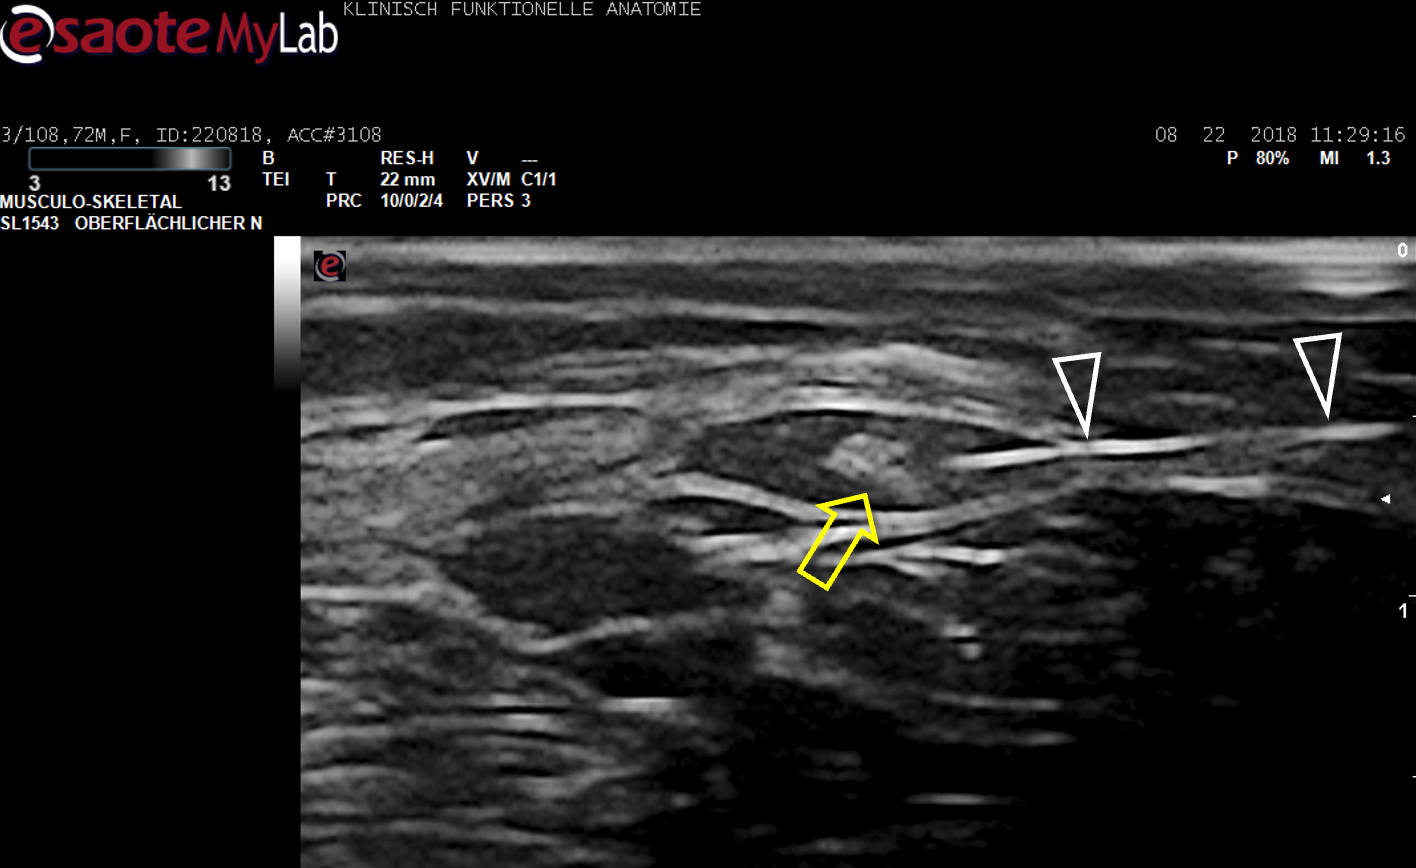

Der hell erscheinende N. cutaneus femoris lateralis (Pfeil) wird am Oberschenkel in seinem „fettgefüllten Flachtunnel“ (im US dunkel!) am leichtesten aufgefunden: “POV“ (Point of Optimal Visibility) nach Prof. Moriggl.